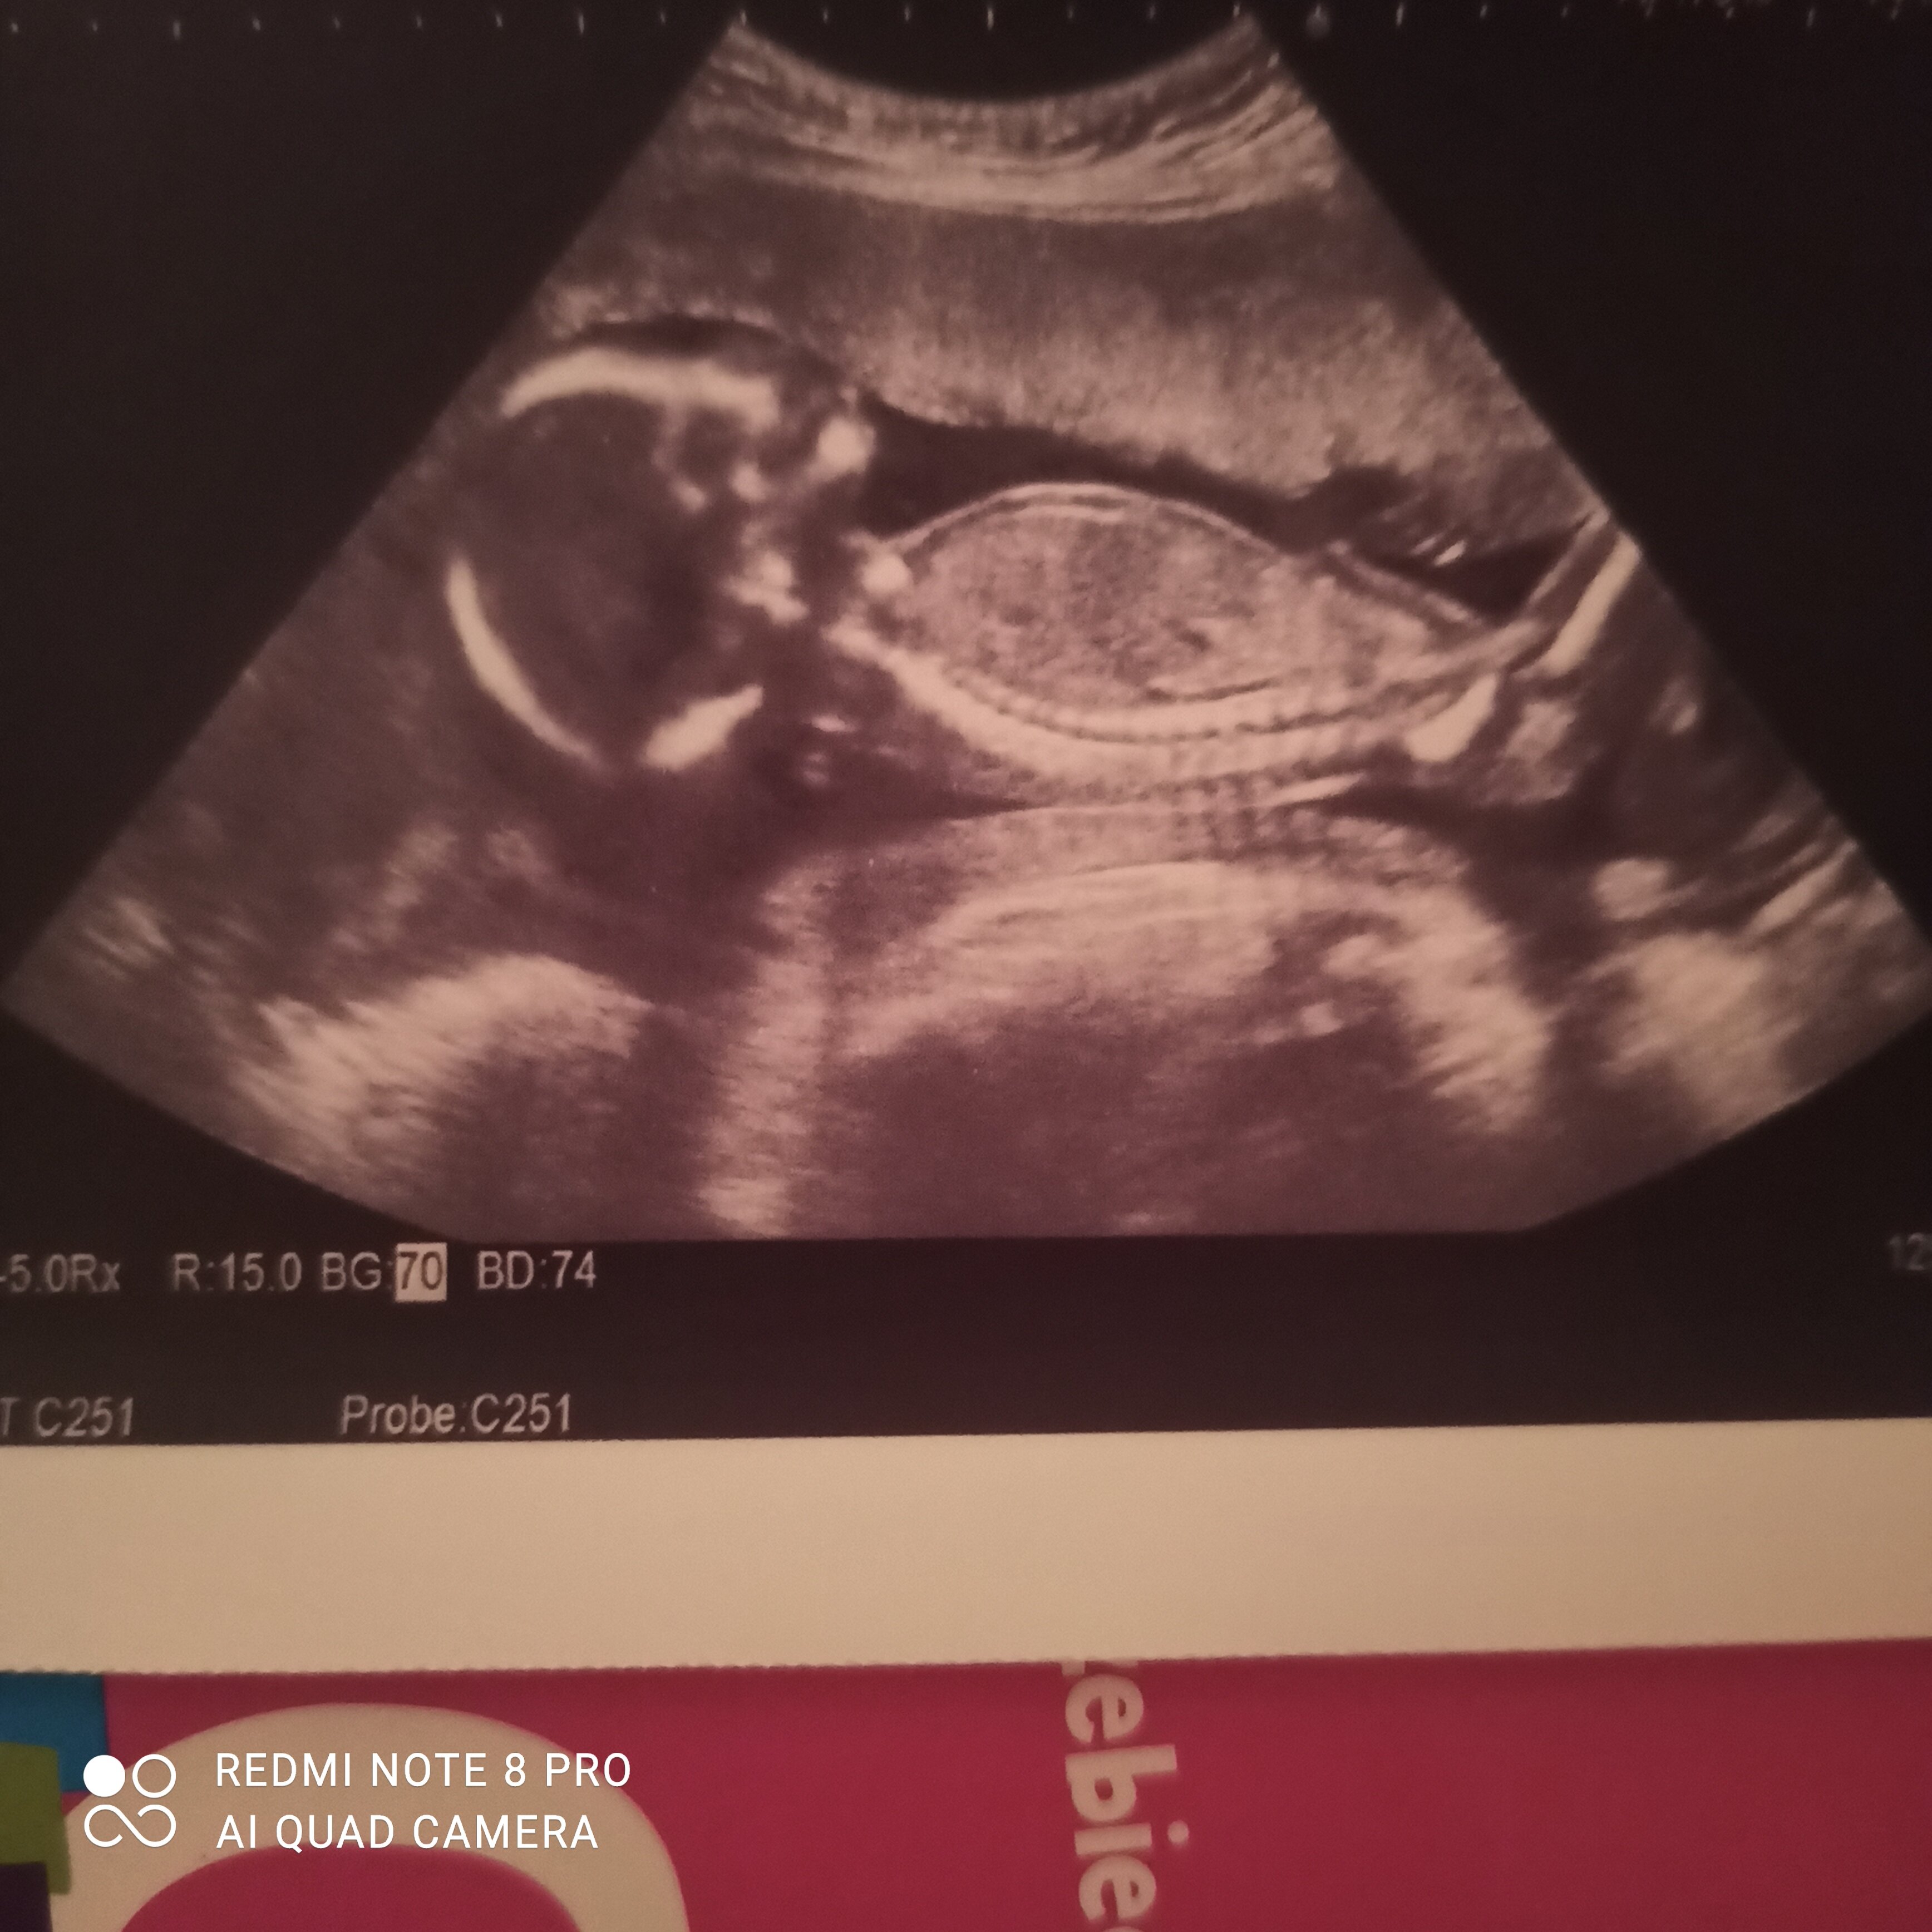

Płeć dziecka z usg

Witam czy ktoś jest w stanie dostrzec jaka to jest płeć?

• IMG_20221128_170854.jpg

974 KB · Wyświetleń: 368

Na FB jest grupa rozpoznawanie płci metoda ramzi i nub, zapytaj tam ;)